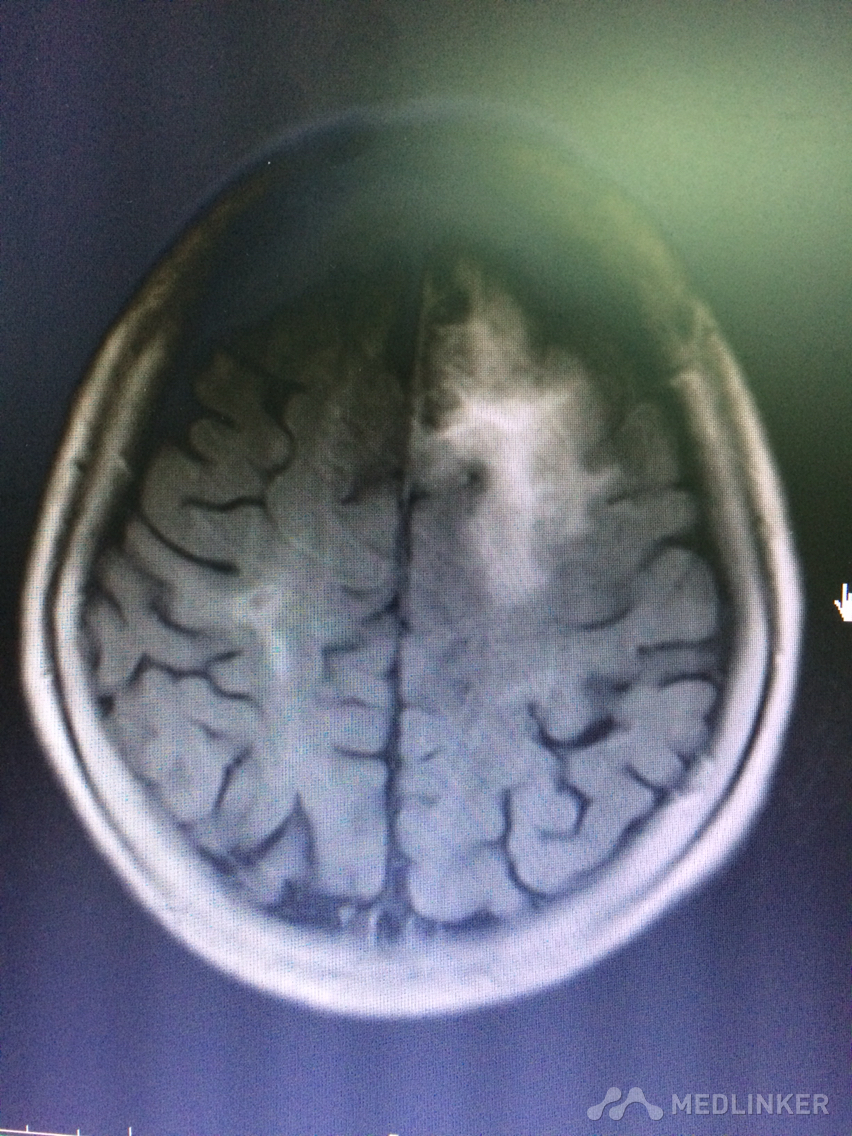

看看这MRI,奇怪啊,快来帮忙看看?

患者78岁老年女性,以精神行为异常和认知障碍为主要表现